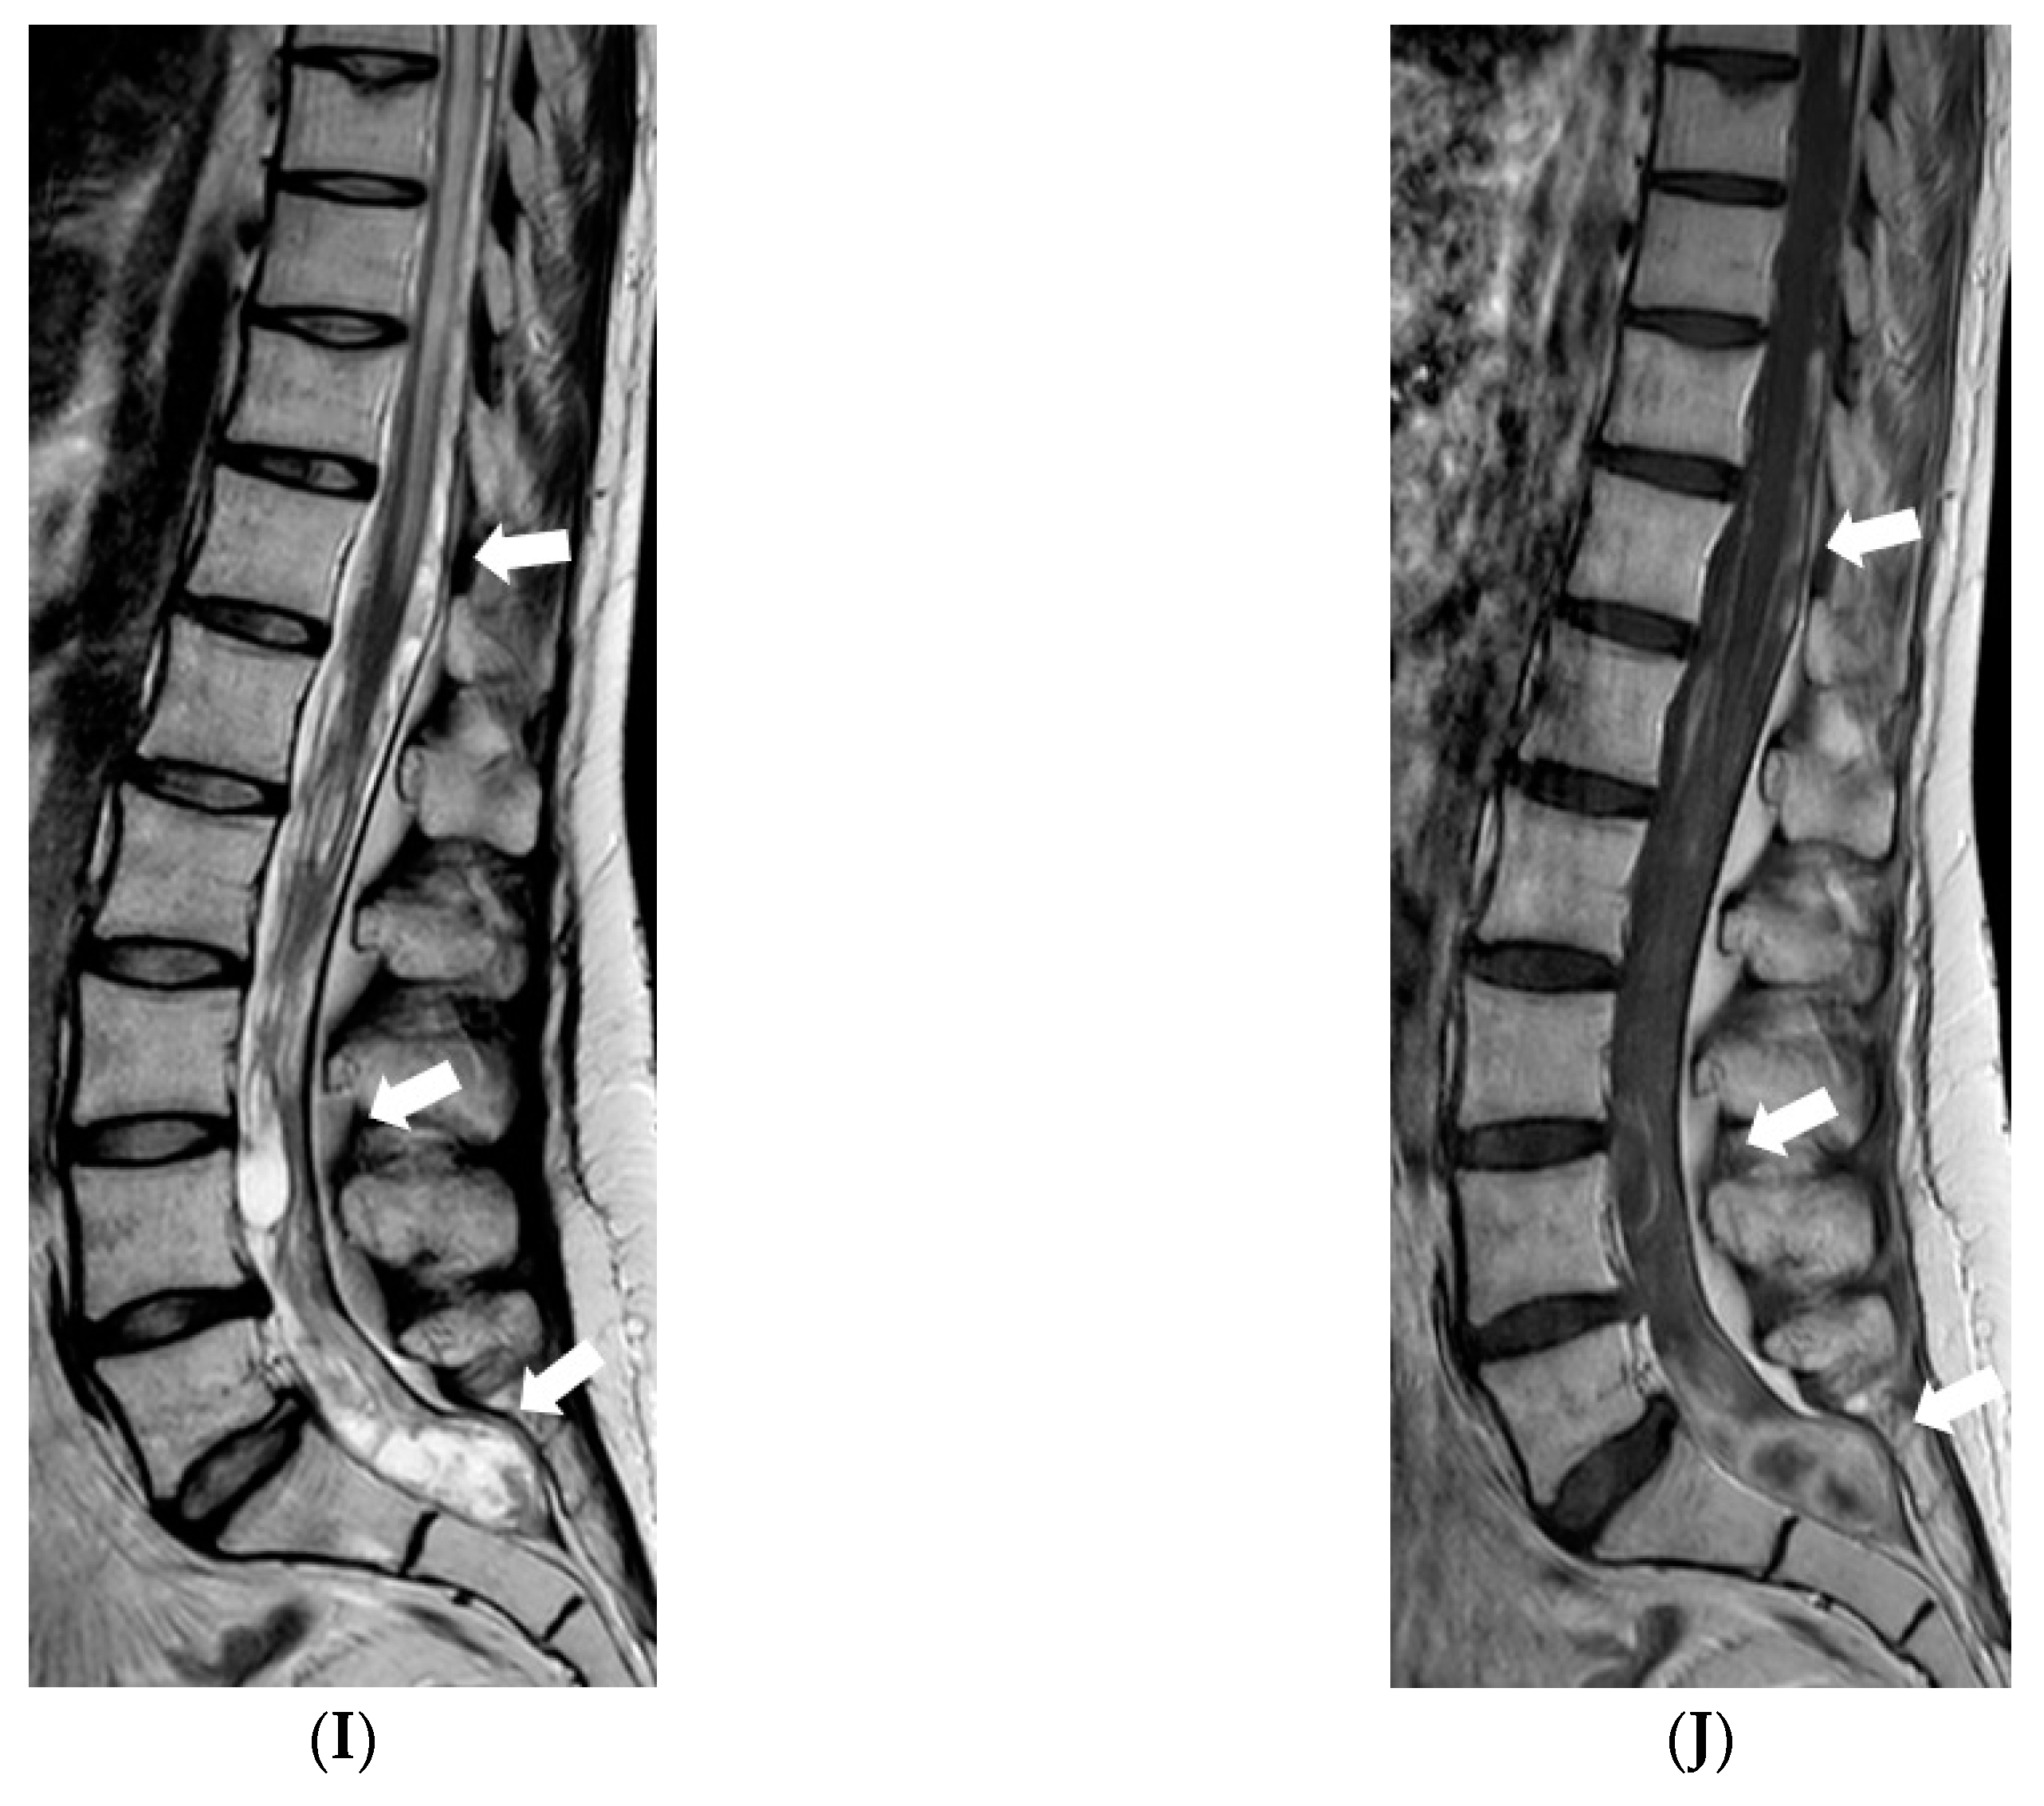

In July 2011, a 16-year-old girl was admitted to Hospital of Lithuanian University of Health Sciences Kauno klinikos due to severe headache, vomiting, and vertigo lasting 2 days. She had a half-year history of similar paroxysms usually beginning with numbness in hands or in one side of face or leg. Neurological examination revealed right-sided peripheral facial paresis, horizontal nystagmus, painful exit points of branches of the right trigeminal nerve, slight deviation of the uvula to the right, right-sided hemiparesis, and cerebellar ataxia. Moreover, papilledema was observed. Brainstem evoked potentials response audiometry showed no clear waves on the right side although hearing was normal. Magnetic resonance imaging (MRI) of the head demonstrated a hyperintense mass on T2W/FLAIR images with heterogenous enhancement in the right cerebellopontine angle cistern and internal auditory canal (Figure 1). All figures in this manuscript are non-published and original.

Figure 1.

Initial MRI of the brain at our clinic (July 2011): (A) Axial T2W/FLAIR and (B) coronal T2W images demonstrate a hyperintense mass in the right cerebellopontine angle cistern and internal auditory canal. (C) Axial and (D) coronal T1W postcontrast images show heterogenous enhancement in the referred area.

Five months after the first MRI, another MRI was performed, and it showed a new small enhancing nodule in the prepontine cistern at the pontomedullary junction, in the expected location of the left abducens nerve (Figure 2).

Figure 2.

Follow-up MRI of the brain after the surgery (in December 2011). Axial post-contrast T1W image demonstrates a new enhancing nodule in the expected location of the cisternal segment of the left abducens nerve.